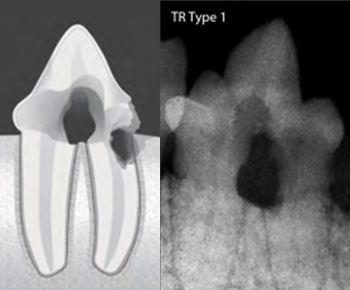

치아흡수병변 TYPE 및 예시

TYPE 1

정상 치아의 모습과 치아엑스레이 영상

치아흡수병변의 모습과 치아엑스레이 영상(Type1)